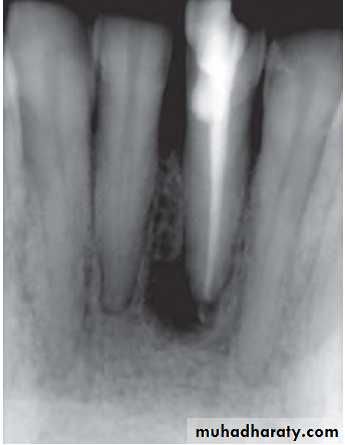

• Radiographs show large area of radiolucency in the apex created by inflammatory connective tissue which has replaced the alveolar bone at the root apex

Radiographic Features

• Mostly discovered on routine radiographic examination• The earliest change in the periodontal ligament is found to be thickening of ligament at the root apex

• Lesion may be well circumscribed or poorly defined

• Size may vary from small lesion to large radiolucency exceeding more than 2 cm in diameter.

• Some amount of root resorption has been reported.